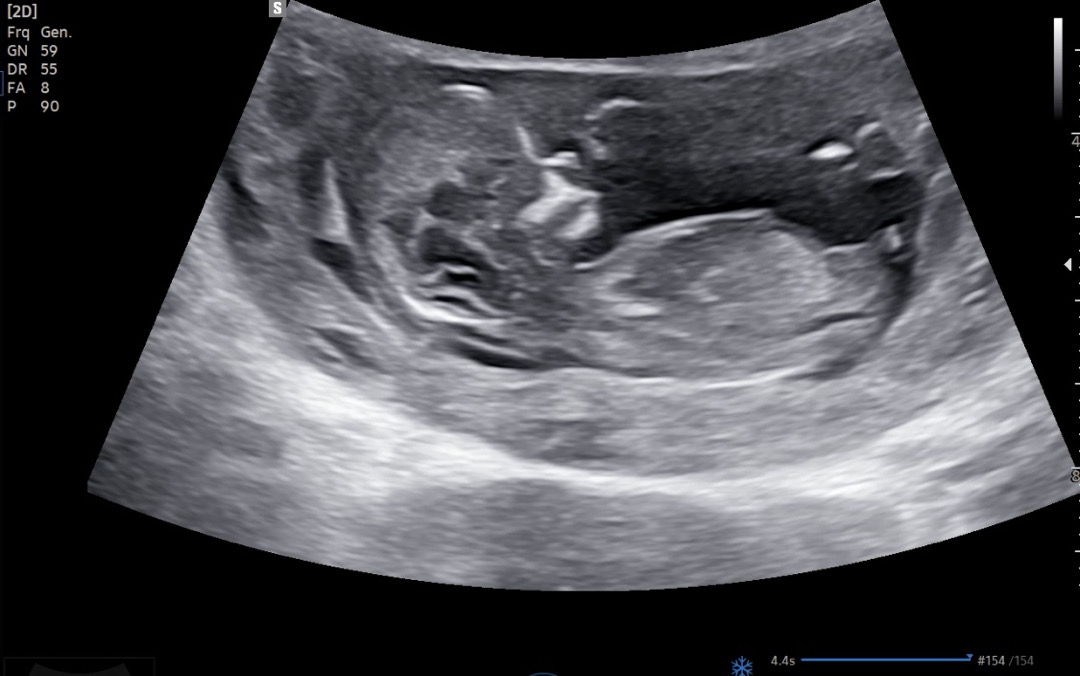

12주 5일차 아들일지 딸일지?한번만 부탁드려요🥹🥹

12주 5일차 입니다!! 보일까요? 한번씩만 투표 부탁드려요 복 많이 받으세요🥰🥰